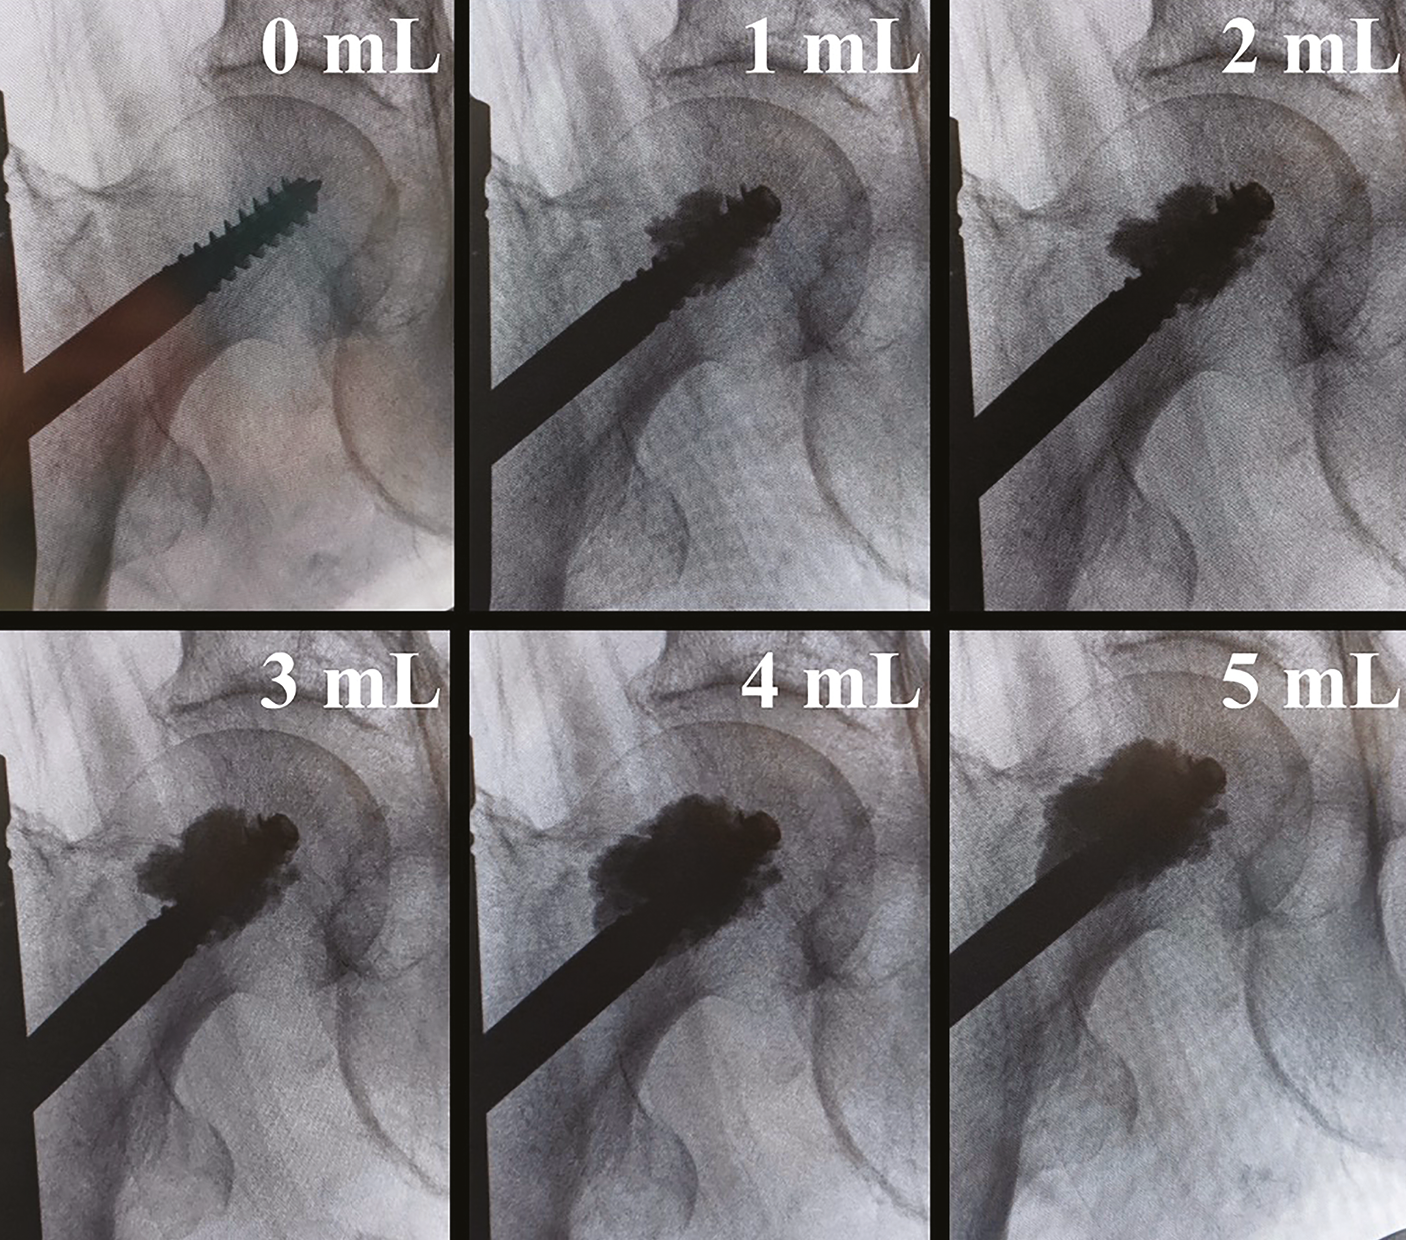

Very regular fluoroscopic checks should be made during augmentation to monitor the diffusion of cement into the femoral head (Figure 5).

DePuy Synthes recommends an augmentation of between 3 and 6 mL of cement. The theoretical maximum volume of augmentation with one kit (3 boxes) is 7 mL.